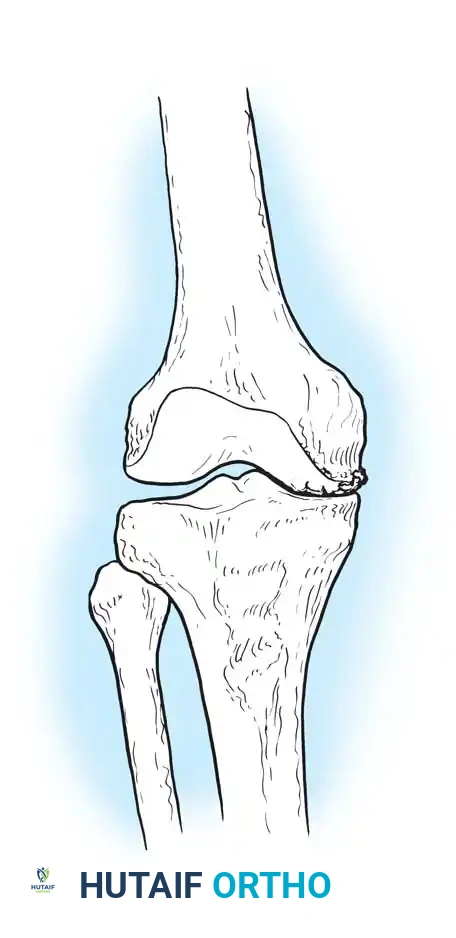

When osteoarthritis is unicompartmental and associated with mechanical malalignment (varus or valgus), corrective osteotomy is a powerful joint-preserving procedure. By realigning the mechanical axis, load is transferred from the diseased compartment to the relatively healthy compartment.

High Tibial Osteotomy (HTO)

HTO is primarily indicated for medial compartment osteoarthritis associated with varus deformity. The goal is to shift the mechanical weight-bearing axis slightly lateral to the midline of the knee joint (the Fujisawa point, typically 62% of the tibial width from the medial edge).

Surgical Atlas: Osteotomy and Realignment Biomechanics

The following radiographic and illustrative figures detail the preoperative planning, biomechanical axes, and intraoperative fixation strategies critical for successful osteotomies around the knee.

Preoperative templating is mandatory. The mechanical axis must be drawn from the center of the femoral head to the center of the ankle mortise. The degree of correction is calculated to ensure the new weight-bearing line passes through the targeted compartment.